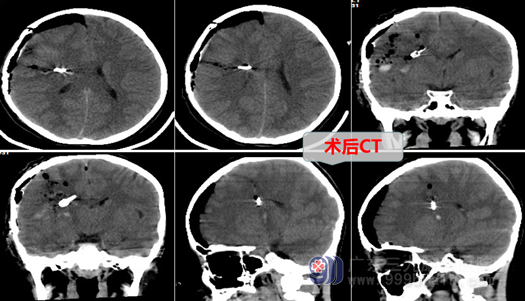

住入神经外十科后,很快做了CTA检查,结果显示:右侧额叶脑出血并破入蛛网膜下腔,基底节区动静脉畸形(AVM),脑血管DSA显示:基底节区AVM伴发动脉瘤,由豆纹动脉供血,静脉回流至脑深部直窦,病变不适合做栓塞治疗,只能开颅手术,但手术也确实是有比较大的风险。完善术前检查后,欧阳辉带领团队认真讨论,制定了周密的手术方案,决定在全麻下行右侧豆纹动脉远端动脉瘤夹闭术+右侧额叶动静脉畸形切除术及血肿清除术。术中他们如履薄冰、如临深渊,小心翼翼,在显微镜放大下,顺利夹闭了动脉瘤,切除了畸形血管,清除了血肿,现在小女孩已顺利进入康复期。